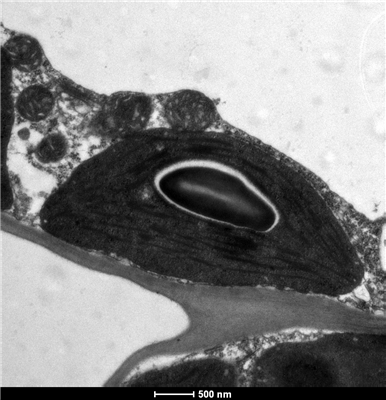

簡(jiǎn)要描述:掃描電鏡是1965年發(fā)明的較現(xiàn)代的細(xì)胞生物學(xué)研究工具,它具有制樣簡(jiǎn)單、放大倍數(shù)可調(diào)范圍寬、圖像的分辨率高、景深大等特點(diǎn)。近年來,掃描電鏡已廣泛地應(yīng)用在生物學(xué)、醫(yī)學(xué)、等學(xué)科的領(lǐng)域中。

掃描電鏡為物體表面結(jié)構(gòu)成像,具有分辨率較高,可方便快捷地進(jìn)行高真空模式與低真空、熱模式之間的轉(zhuǎn)換,放大倍數(shù)范圍寬,從5×到300000×,而且樣品室空間和觀察視野大,對(duì)樣品觀察以從宏觀到納米尺度,裝置所搭載的能譜分析儀EDS將所測(cè)信號(hào)通過計(jì)算機(jī)系統(tǒng)進(jìn)行數(shù)字化,可以在短時(shí)間內(nèi)對(duì)樣品進(jìn)行元素分布分析。